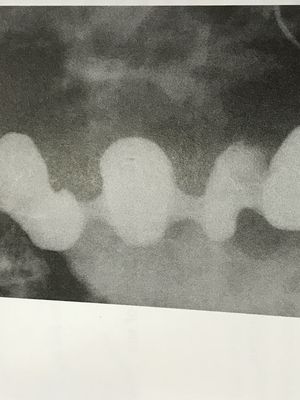

What is the diagnosis of this patient ?? 🤔

Diffuse esophageal spasm